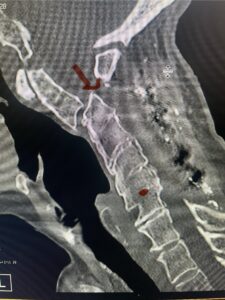

This is a 59 year-old female with a history of cerebral palsy and a prior C3-C7 posterior cervical laminectomy and instrumented fusion two years prior. She did ok until she developed progressive weakness of all four extremities and numbness. Imaging revealed she had a significant breakdown above the fusion at C2-3 with a grade 2-3 spondylolisthesis of C2 on C3 with severe spinal cord compression (Fig. 9). It was surprising the degree of anterior fusion induced by the posterior fusion from C 3-C 7 (Fig. 10). Because of her progressive neurological dysfunction in a patient who was already compromised because of her cerebral palsy, it was clearly necessary to decompress from occiput to C 3. We utilized her prior lateral mass screws although we removed bilaterally the C7 screws to reduce the fulcrum-effect on the C7-T1 junction as the C 6-7 level was solidly fused. We performed an occiput to C 6 fusion with occiput to C3 laminectomy (Fig. 11) Post operatively we had good placement and alignment (Fig. 12) The patient went to rehab with improvement of strength and numbness particularly in hands.

Fig. 10: Sagittal cervical CT scan demonstrating grade 2-3 subluxation of C2 on C3 above prior C3 to C7 posterior instrumented fusion and laminectomy (red arrow). Note the unusual significant anterior auto fusion resulting from prior posterior construct (red dot).